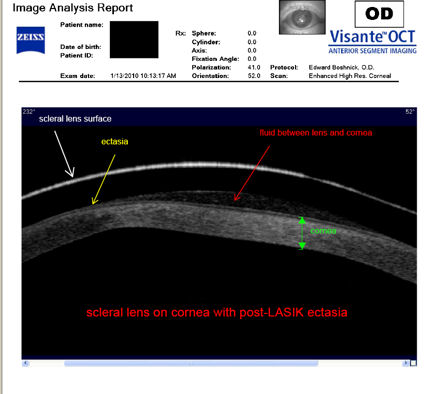

Следующие изображения были получены с использованием метода, называемого оптической когерентной томографией, или ОКТ. Прибор позволяет получить изображение в поперечном сечении путем сканирования передней части глаза (переднего сегмента) лучом света. Думайте об этом как об ультразвуке, использующем свет вместо звуковых волн для создания изображения живых тканей.

На снимке ниже показана роговица пациента, у которого после операции LASIK развилась эктазия. Пациент носит жесткие склеральные контактные линзы. Вы можете видеть выпячивание роговицы в самом слабом месте (эктазия), что приводит к сильному искажению зрения. Очки и мягкие контактные линзы неэффективны для таких глаз, как этот. Нажмите на изображение, чтобы увеличить.

На следующих двух снимках ниже показана жесткая склеральная контактная линза на роговице после операции LASIK.

Изображения любезно предоставлены доктором Эдвардом Бошником, который посвятил свою практику восстановлению качественного зрения и информации о эктазия после операции LASIK .